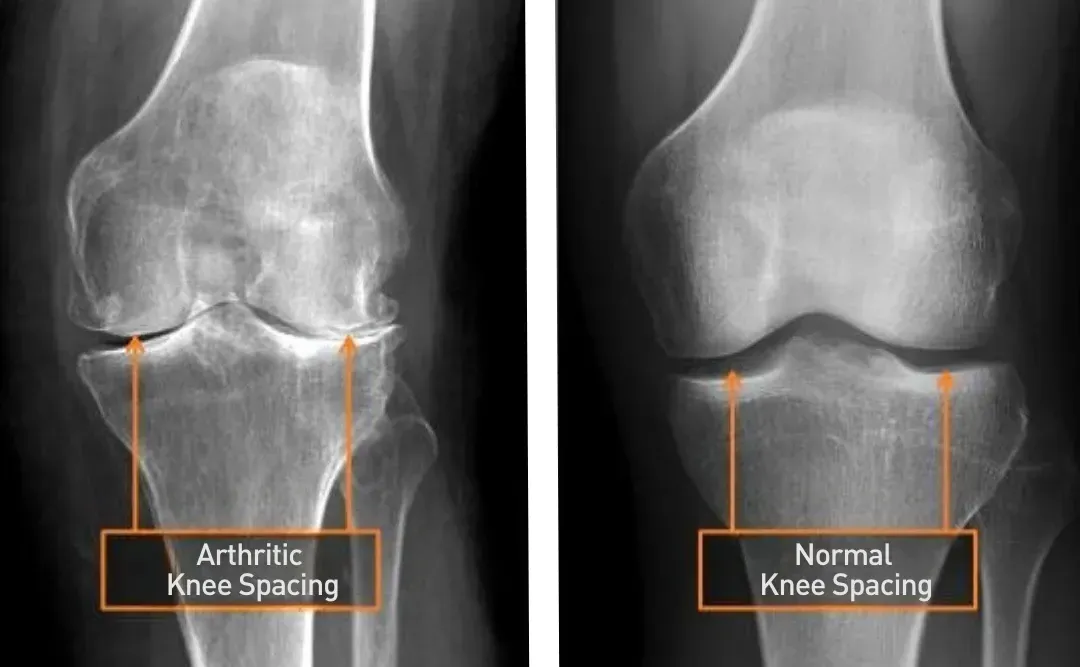

Ignoring knee pain often leads to worsening joint damage, reduced function, and increased discomfort. Conditions like arthritis, meniscus tears, tendonitis, bursitis, or persistent crunching and popping sounds are common contributors to knee pain, making even basic movements a challenge.